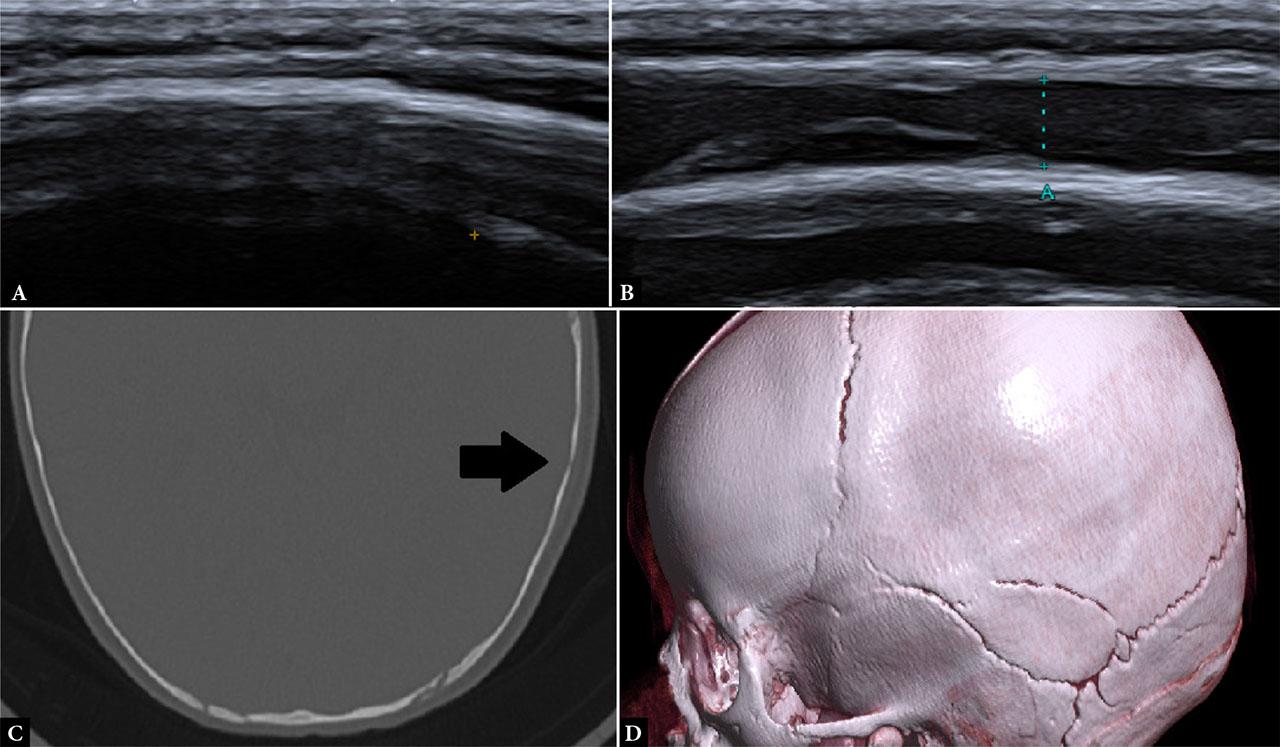

All patients were first clinically evaluated by a pediatric surgery resident or specialist in the emergency department. Based on surgical assessment, patients were referred to the radiology department, where ultrasound examinations were performed in a dedicated ultrasound room using a CANON Aplio i700 ultrasound machine, equipped with a high-frequency linear transducer (11–18 MHz). Children were positioned supine or, in cases of occipital trauma, in a prone or sitting position, accompanied by a caregiver, with gentle immobilization applied when necessary to minimize motion artifacts. The area of impact, hematoma, or maximal tenderness was systematically scanned in both longitudinal and transverse planes, with additional sweeps of adjacent and contralateral regions for comparison. In the absence of clear clinical signs of impact area, or problems with indicating the expected site of injury (non-verbal children), a broader portion of the skull was routinely examined. Particular attention was paid to differentiating fracture lines from normal cranial sutures at the affected site by tracing sutures to a fontanelle where possible or by comparing with symmetric contralateral structures. Major cranial sutures were assessed only at the affected site and adjacent collateral locations to distinguish normal suture lines from potential diastasis. ( Fig. 1, Fig. 2, Fig. 3, Fig. 4) No cases of sutural diastasis were identified in the cohort. All scans were performed by 15 radiology department physicians, either trained pediatric radiology residents or board-certified specialists. Interobserver variability was not formally evaluated.

Left parietal bone fracture. A. Ultrasound examination revealed a subtle cortical discontinuity and deflection of the outer table. B. A subperiosteal hematoma was visible along the parietal bone. C, D. CT examination performed the following day confirmed the diagnosis, demonstrating a linear fracture fissure (arrow in C) of the parietal bone